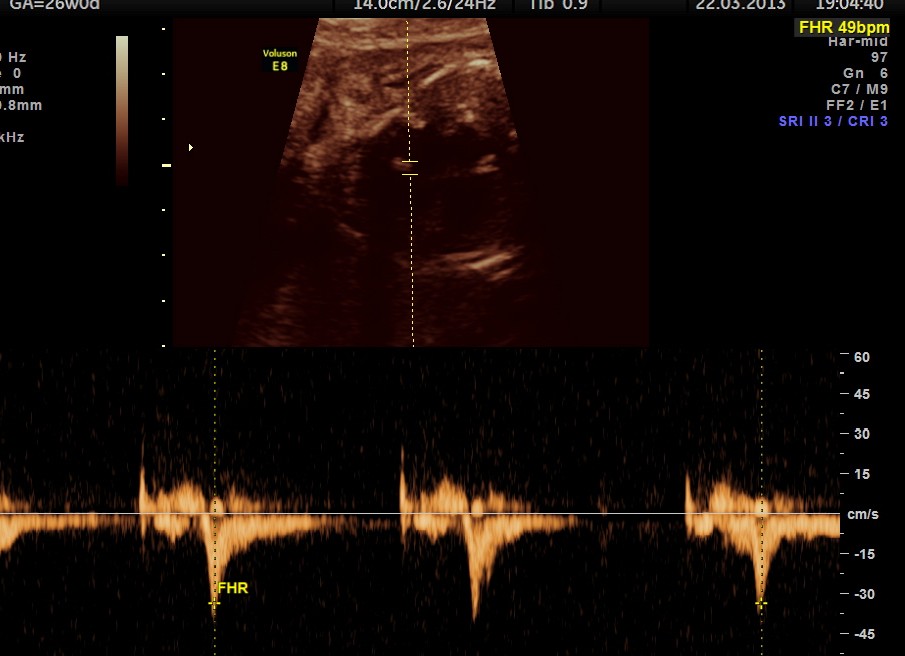

this fetus showed intermittent A.V.DISSOCIATION, BRADYCARDIA AND NORMAL RHYTHM

the following picture shows A.V.DISSOCIATION ( ventricular beats above and atrial below)

ventricular rate( above mid line ) is 96 bpm ;

atrial rhythm ( seen below base line ) shows dissociation

the following picture shows a probable transmitted rhythm with severe bradycardia